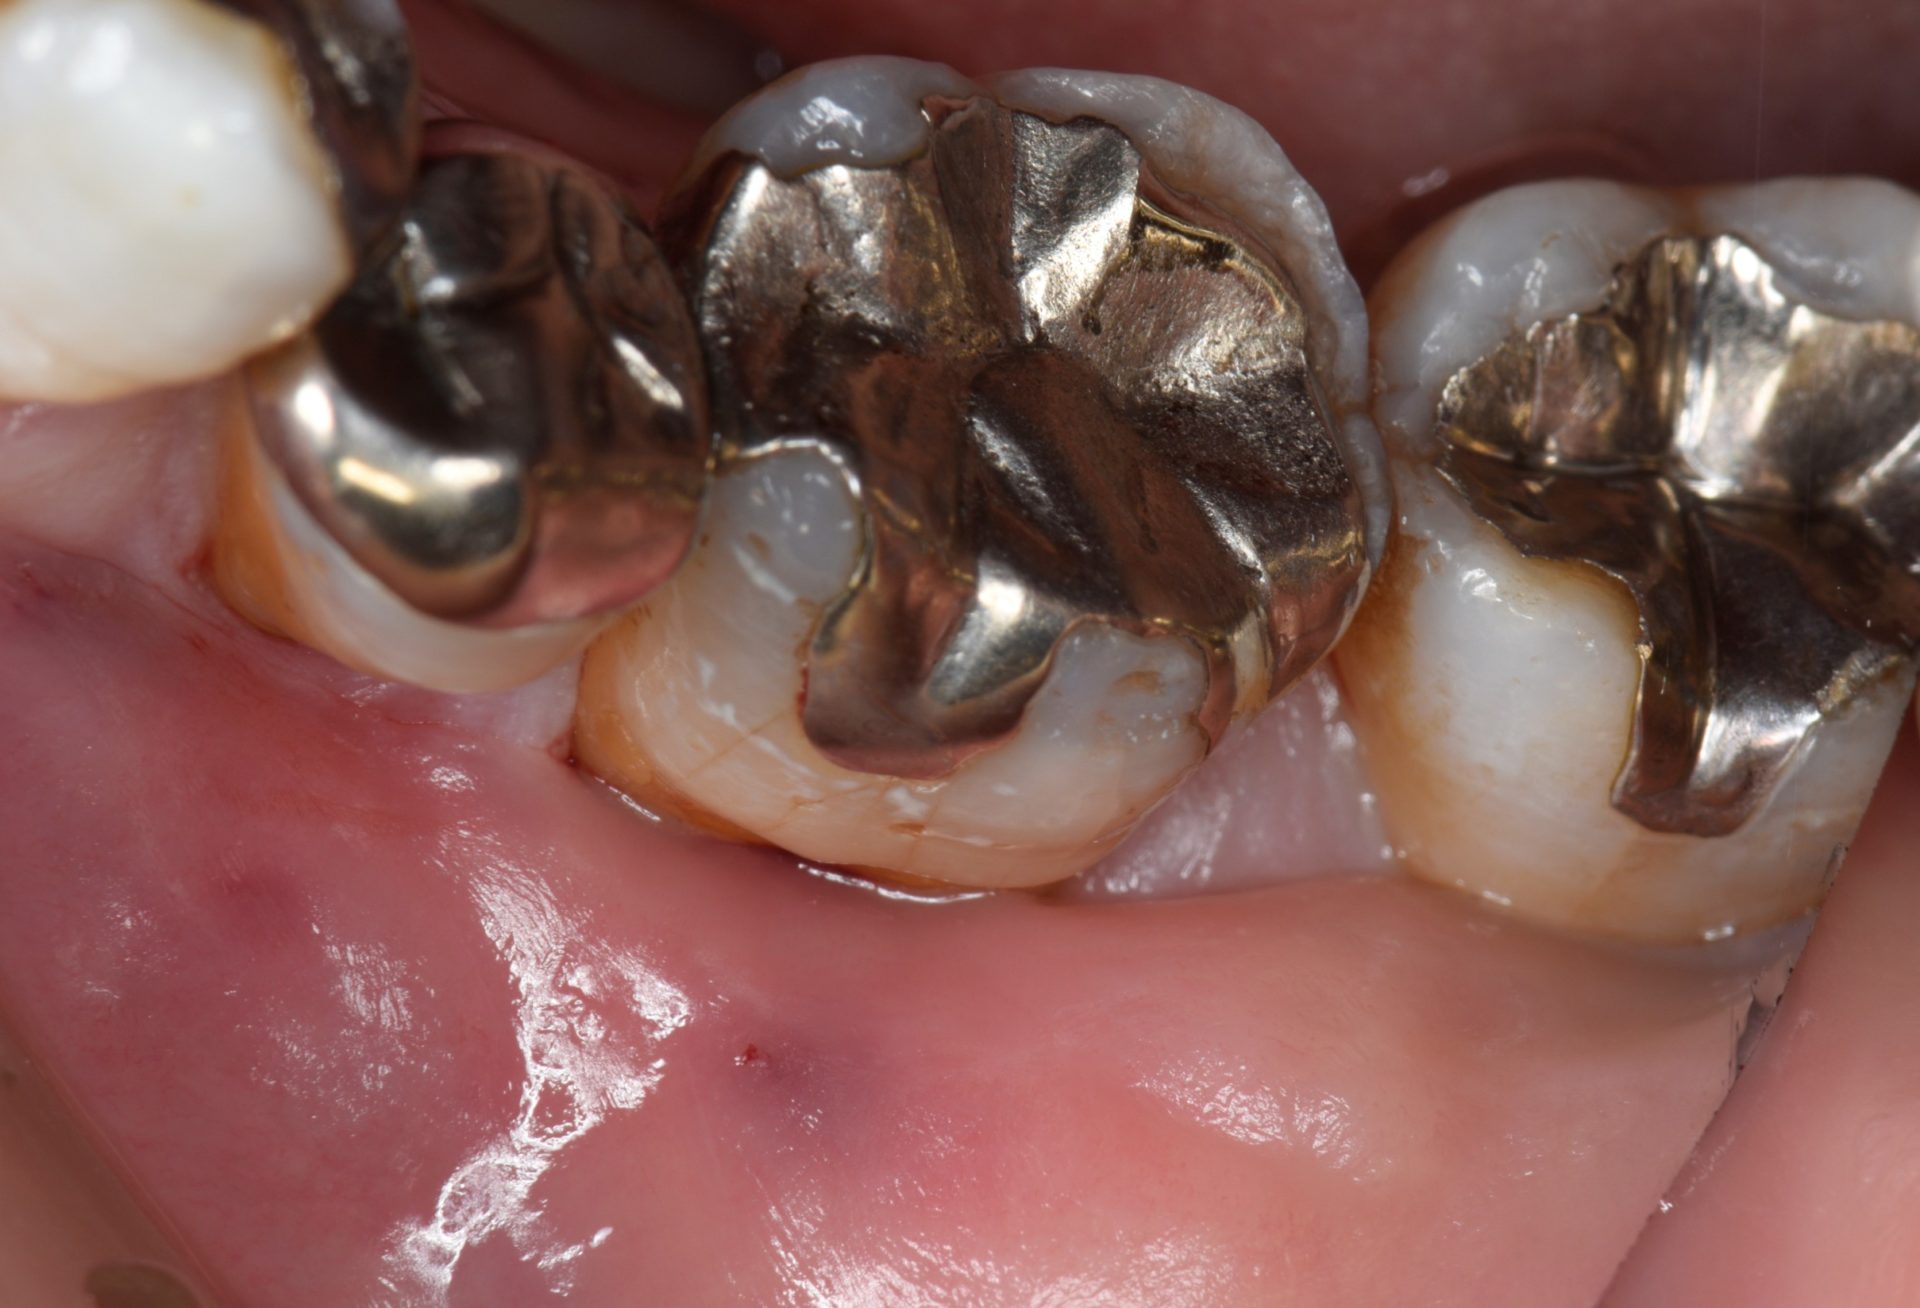

まずはこちらの写真をご覧ください。

この方は50代の女性です。

二本の歯に、茶色い点状の虫歯があります。

この二本だけに同じような虫歯ができていますね。

実はこの二本の歯だけ、はえぎわの歯茎が柔らかい粘膜になっています。

上から見た写真です。

柔らかい粘膜がせり上がり、歯の側面に乗ってしまっています。

こんな粘膜と歯の間にはプラークがたまりやすくなります。

ここはちょうど虫歯ができていたところですよね。